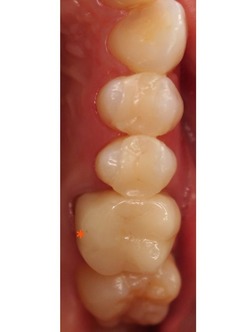

下顎左側の奥歯です。

この部分は、少し前のブログでもアップしました。

コンポジットレジン(CR)による治療です。

健康保険が適応されるのも利点ですね。

下顎左側の*印の歯の治療ステップを見てみましょう。

削った穴につめたCRをきれいに研磨し、終了です。

以下は、治療後の上下顎の写真です。